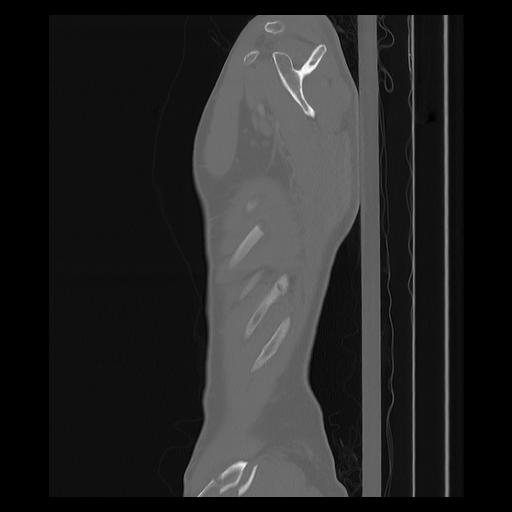

33 PULMON,CE,Sagittal,3.000,PULMON,Sagittal,